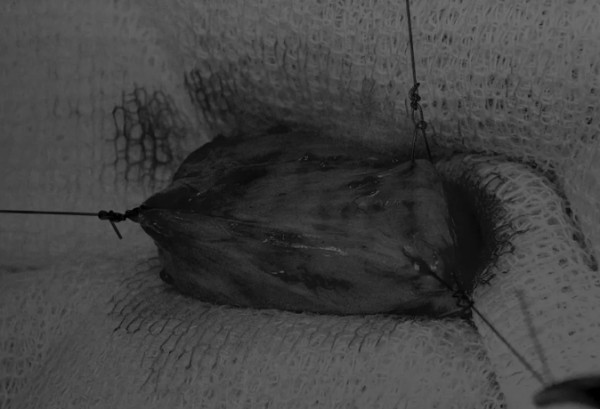

在牵引缝线之间选择血管扩张较差的区域用手术刀切开膀胱壁(图3)。在牵引缝合线之间用手术刀在血管不良的区域做切口。切开膀胱壁后,膀胱内的手术可按手术方案实施,例如取出结石(图4)。

图3 避开主要的膀胱血管,做一个尽可能小的切口